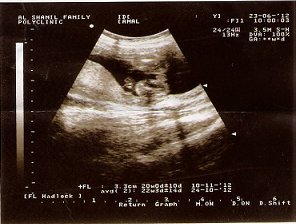

تصدقون هبلوا فيني هالمستشفيات ... فاطمه عطيه في الشامل تقول حامل بولد ... والعسكري يقول بنت .. والاحد العام يقول بنت .. واحساسي يقول ولد ... على فكره ترى عندي ولد وبنت يعني مو قضيه ..

هذي صور السونار عند فاطمه عطيه ....واحكموا ..السونار الثاني تقول ان الدائره هي (.....) للولد ..